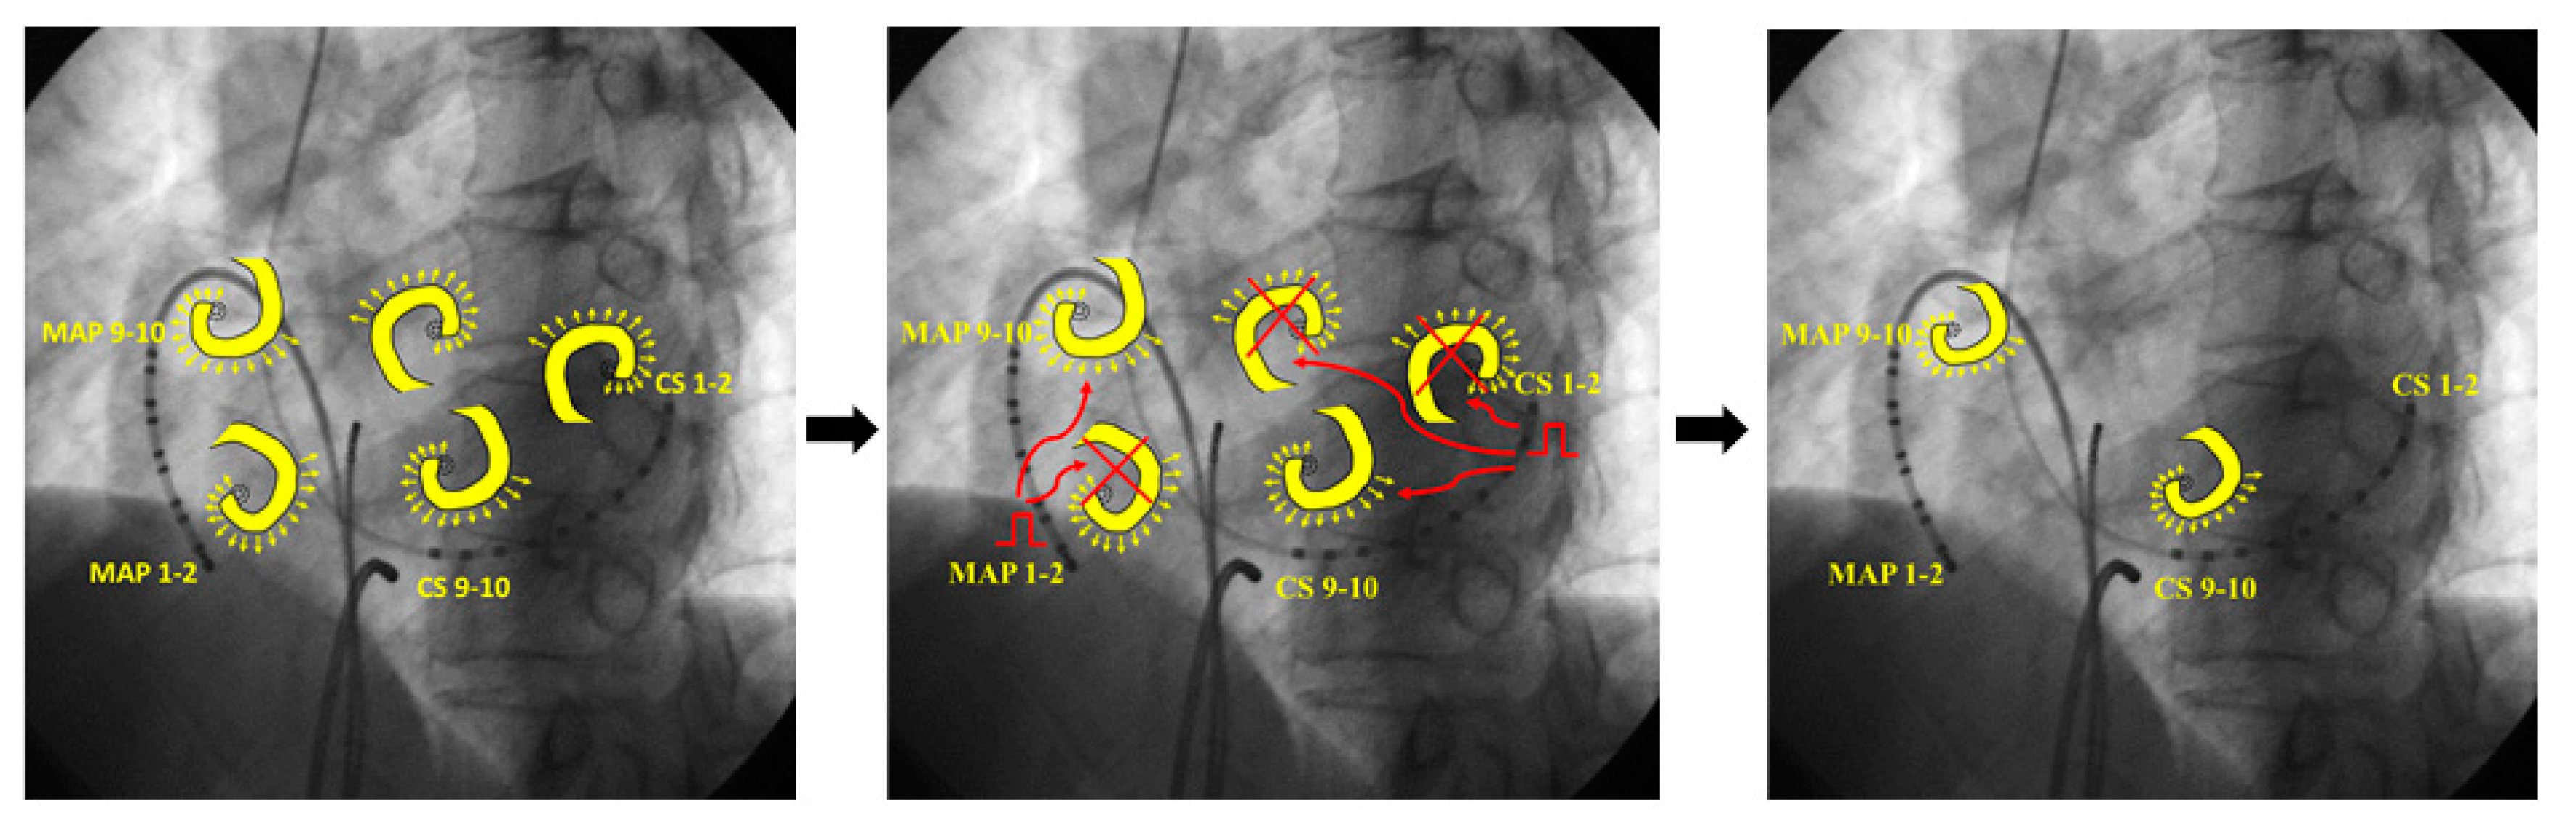

3.2. Representative Cases

3.2.1. Case 1: 42-Year-Old Man with Symptomatic PAF

3.2.2. Case 2: 72-Year-Old Man with Symptomatic PAF

3.2.3. Case 3: 67-Year-Old Man with Symptomatic PAF

4.1. Mechanism of AF Termination

- (A)

- (B)

- (C)

- Leading circle theory [14]; The presence of an excitable gap is well known for the maintenance of AF. Pacing stimuli entrain and fill the excitable gaps of tachycardia, affecting the refractory period. Eventually, AF is unable to sustain itself and thus terminates slowly.